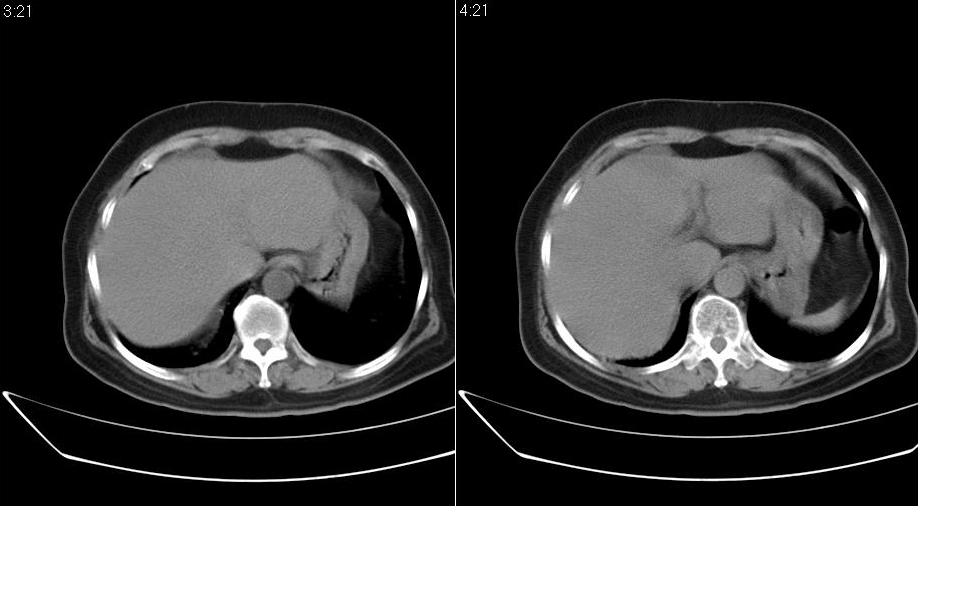

女 67岁,以腹疼就诊,不发热,八年前有肠梗阻病史,炎热的夏天,下午又吃了两块西瓜及两个桃子,以后无大便,不放屁。

右侧腹部膨隆左侧塌陷,小肠积气积液扩张,肠袢迂曲扭转,远侧肠曲无异常,考虑高位肠梗阻,小肠扭转可能,具体可能为3、4组,建议扫描全腹。此外胆囊大。先对症保守治疗,必要时手术。

腹内疝很罕见的,此处可发生盲肠旁疝但不符。那个是粪石??